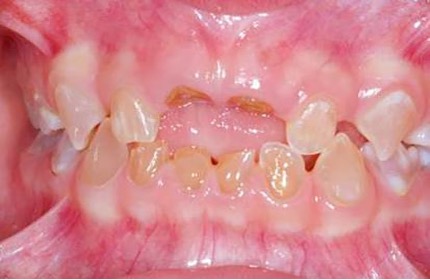

El examen clínico intraoral reveló alteración de la estructura y color de las piezas primarias, atrición y pérdida de la dimensión vertical (Figura 2). Radiográficamente se observó la presencia de coronas con marcada constricción cervical y raíces cortas (Figura 3). Presentaba alto riesgo cariogénico, por la presencia de lesiones de caries activas y dos restos radiculares, sumado a la anomalía estructural de la dentina (riesgo biológico específico) y bajo riesgo gingivoperiodontal. El riesgo socio-económico era alto por provenir de una familia con marcadas limitaciones económicas. Luego de la anamnesis, examen clínico y radiográfico, e interconsulta con el médico de cabecera se estableció el diagnóstico de DI Tipo I asociado a OI tipo I. Se planificó un tratamiento integral y preventivo con los objetivos de devolver forma y función, y proteger y evitar el desgaste de los tejidos conductas que pudieran interferir con el tratamiento.

Figura 2: Examen clínico intraoral del maxilar superior e inferior y vista anterior. Año 2007

En la radiografía panorámica de control del año 2015 se observó la progresiva obliteración del conducto radicular en el grupo incisivo superior e inferior y en los primeros molares permanentes; presentado los premolares en erupción, un conducto radicular anormalmente amplio en toda su longitud (Figura 8). En la del año 2018 se visualizó la continua aposición de dentina a nivel radicular que obliteró en forma casi total los conductos de la mayoría de las piezas dentarias, a excepción de los segundos molares inferiores (Figura 10).

Cuando la dentición permanente está implicada, los incisivos inferiores son los más comprometidos, presentando en estos casos una coloración intensa propia de la DI (O’Connell, Marini 1999, Majorana, Bardellini et al. 2010, Petersen, Wetzel 1998), como se observa en el paciente. Las piezas permanentes fueron monitoreadas desde su erupción, recibieron protocolos preventivos con barnices fluorados, pastas y enjuagatorios fluorados domiciliarios, conjuntamente con un adecuado control de higiene oral.15